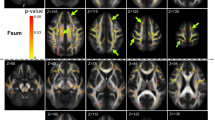

No changes were observed at D70, i.e. an age at which Sod1G86R mice are devoid of motor symptoms5 (Fig. 1). A markedly elevated R2* value in the cervical spinal cord was the first significant abnormality at D85, when the mice became symptomatic in the limbs (relative to controls)5. At D100 (shortly before death at D110), a significant decrease in the volumes of the cervical spinal cord and the motor cortex was noted (relative to controls). The change in iron was no longer significant.